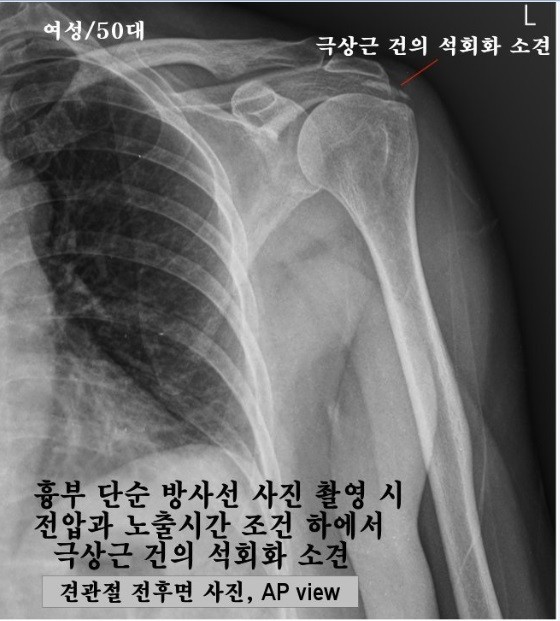

이날 감정위원들은 14개의 감정항목을 결정했다. 이 가운데는, 주신씨 명의 엑스레이 사진에서 볼 수 있는 흉추1번-경추7번 극상돌기 배열방향의 차이, 흉곽의 비율 등이 포함돼 있다.

- ▲ 최대집 의혁투 공동대표가, 엑스레이 촬영위치 및 각도의 차이에 따라 극상돌기의 방향이 다르게 보일 수 있는 지를 확인하기 위해 실험한 엑스레이 사진. 왼쪽은 AP(전-후면 사진), 오른쪽은 PA(후-전면 사진). ⓒ 최대집 대표 제공.

‘극상돌기’의 경우에도 차이점은 명확히 드러난다.

변호인 측은 “공군에서 찍은 엑스레이와 비자발급을 위해 찍은 엑스레이에서는 피사체의 제 1흉추 극상돌기가 오른쪽으로 휘어있지만, 자생병원에서 찍은 영상에서는 정방향으로 나온다”며, “박주신씨가 공군에 입대해 찍은 엑스레이와 세브란스 공개신검에서 나타난 피사체의 의학적 차이가 명확해 동일인이라고 인정할 수 없다”고 지적했다.

우리가 흔히 등을 만지면, 가운데 뾰족하게 솟아난 부분이 바로 ‘극상돌기’다.

흉추를 비롯해 모든 척추에 존재하며, 흉추에 외상이나 수술, 질병 등이 없었던 근접한 기간 동안 촬영된 엑스레이에서, 극상돌기의 형태가 명확하게 다를 경우, 다른 개체라고 판단할 의학적 근거가 된다.